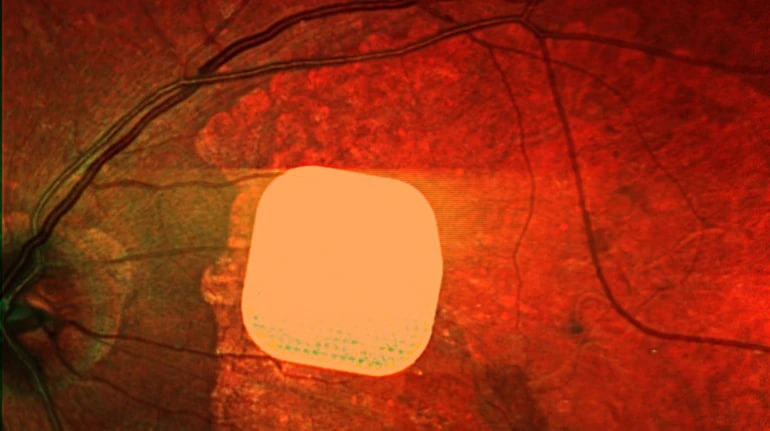

Група міжнародних дослідників розробила новий очний імплантат, який може частково відновлювати центральний зір у людей, які втратили його через важку форму вікової макулодистрофії. Експеримент показав, що технологія дійсно допомагає пацієнтам – 81% учасників відчули покращення, що дозволило їм краще бачити та виконувати повсякденні завдання, такі як читання тексту чи розпізнавання облич. Імплантат розміром лише 2×2 мм вшивається безпосередньо у сітківку ока і отримує сигнали від спеціальної камери, вбудованої в окуляри. Ця нова технологія є першою у своєму роді і може стати значним проривом у лікуванні важких стадій вікової макулодистрофії. Виробництвом імплантату займається американська компанія Science Corporation, яка вже подала заявки на отримання дозволів для клінічного використання пристрою у США та Європі.

Британські лікарі частково повернули зір пацієнтам за допомогою мікрочипа

Британські лікарі з лондонської клініки Moorfields Eye Hospital спільно з колегами з інших європейських медичних закладів провели успішні випробування надтонкого електронного імпланту Prima, який дозволяє частково відновити зір у людей із макулодистрофією – головною причиною втрати зору після 50 років. Цей мікрочип розміром лише 2×2 міліметри встановлюють під сітківку ока пацієнта під час короткої операції. Підключають також систему окулярів доповненої реальності з камерою і мінікомп’ютером. Камера зчитує зображення, перетворює його на сигнал для мікрочипу, який активує клітини сітківки. Після операції 84% пацієнтів знову змогли розрізняти літери, цифри та слова. Лікарі вважають, що ця технологія може значно поліпшити якість життя людей із важкими зоровими порушеннями, дозволяючи їм повернути здатність читати та бути більш незалежними.